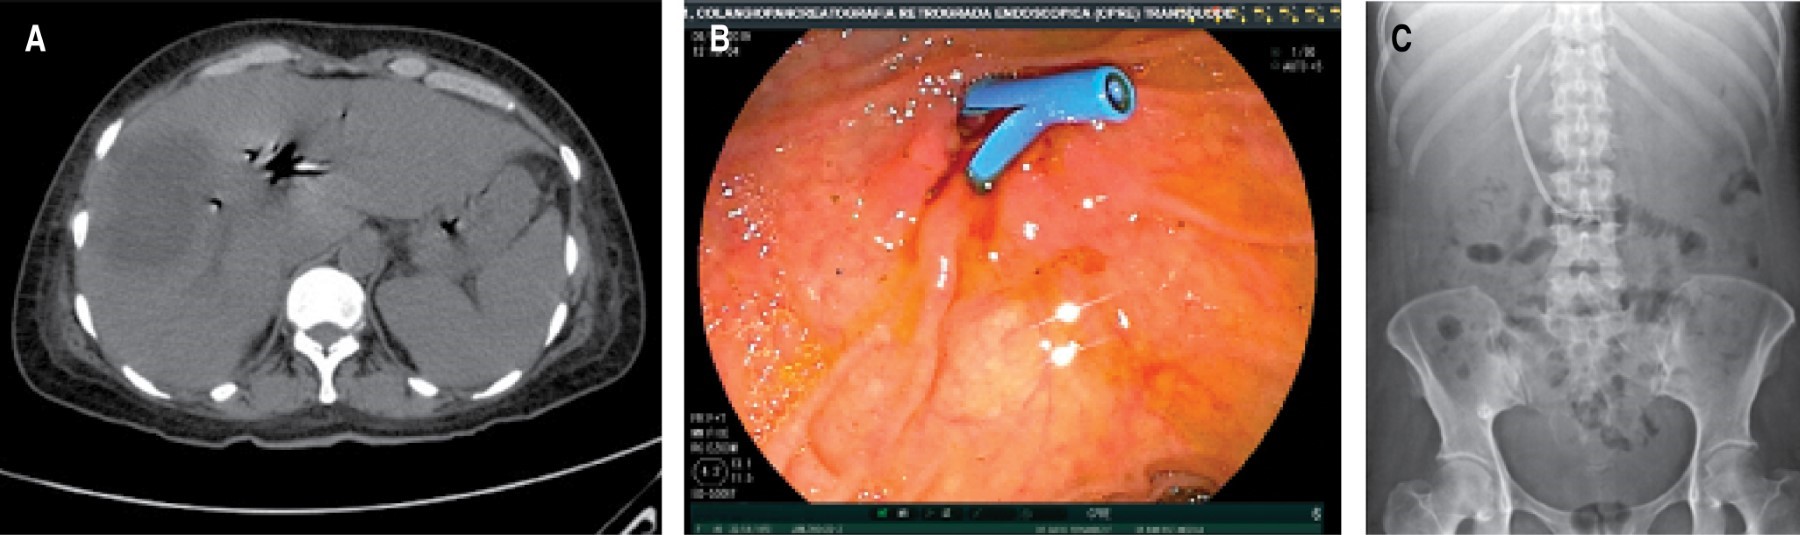

An abdominal CT scan was performed on 10/02/19, which reported findings of a hypodense image of 80 × 53 mm with 23 HU in segments VI and VII concerning liver abscess on the right side, hepatomegaly at the expense of the same lobe, presence of pneumobilia, which is observed in communication with the anterior wall of the gallbladder, little free fluid in the pelvic cavity, bilateral pleural effusion and passive atelectasis. Similarly, ERCP was requested on 10-09-19, which reported a common bile duct of 10 mm, a circular filling defect of approximately 20 mm, which delays emptying the contrast medium from the biliary tract, reporting probable Mirizzi syndrome type IV, and bilioenteric fistula of a site to be determined. Sphincterotomy is performed, sweeping with a lithotripsy cannula and placing a 10 × 10 cm Amsterdam-type stent (Figure 2).

She was sent to our service on 10-27-19, receiving 85% oximetry and anasarca; a chest teleradiography was performed on admission, showing evidence of right pleural effusion of approximately 40%, placing a water seal in the sixth intercostal space with right axillary midline and verifying its placement with a control chest X-ray that ensures the placement of the probe, proposing an exploratory laparotomy on 10-29-19 (Figure 3).